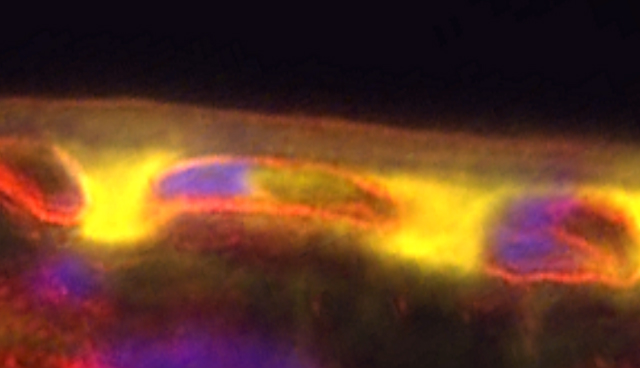

Accumulation of FHR-4 protein (yellow) within the macula

Further investigation, using eye tissue donated for medical research, showed the presence of the FHR-4 protein within the macula - the specific region of the eye affected by the disease.